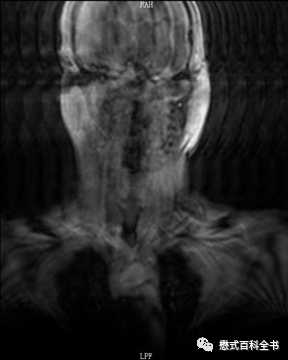

图3~5:Ghosting伪影的表现

一般Ghosting伪影产生的原因主要是硬件系统不稳定导致的。比如:射频系统不稳定、梯度系统不稳定、磁场均匀度等。

Ghosting伪影的图像表现是在相位编码方向出现多个连续的重影(幽灵样影像),这种连续的多个重影还是比较好识别的。